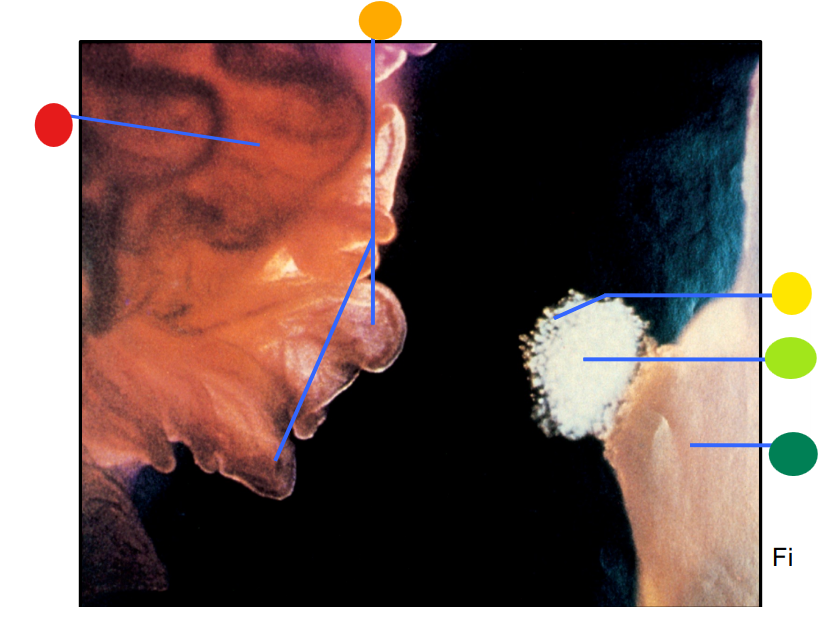

red

infundibulum

orange

fimbriae

yellow

cumulus oophorus

light green

oocyte

dark green

ovary

How is the egg and culmulus oophorus drawn into the infundibulum after the rupture of a mature follicle?

via ciliary action